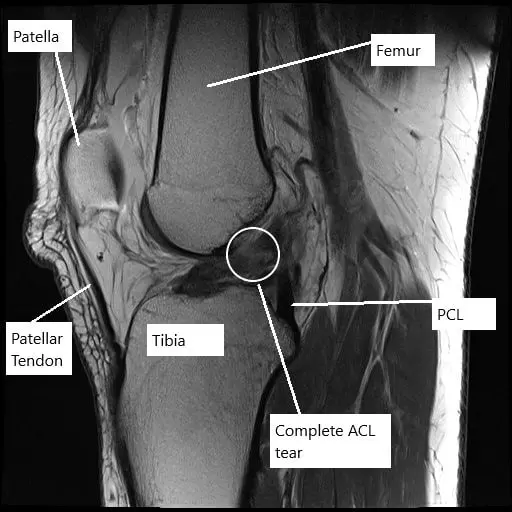

MRI of the left knee showing complete tear of the ACL.

Radiological study in the form of an MRI suggested a complete tear of the ACL along with complex tears of both the medial and the lateral meniscus. The patient desired to be athletically active and to continue her job without any episodes of instability.